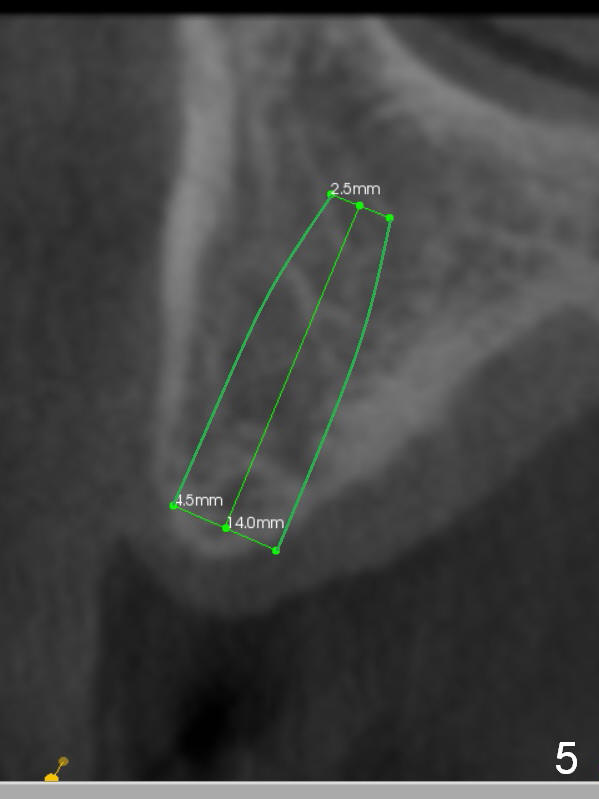

The fearful patient is satisfied with implant placement at #29 and will return to have #5 implant placed. Fig.1 is coronal section of the site of #5 (B: buccal). It shows the narrow crest and low bone density (40-200 Hounsfield unit). Start bone expansion with #15 blade slightly palatal (Fig.2 green line), followed by bone scalpels and bone blades. The latter leads to differential expansion of the buccal and palatal plates (Fig.3 arrows). Once the crestal bone is expanded, use drills or osteotomes (RTs) for deeper portion of osteotomy (Fig.4 red arrow). Finally an appropriately-sized implant is placed (Fig.5). Also prepare bone expanders. Upper Arch Reconstruction, Upper Premolar Immediate Implant Xin Wei, DDS, PhD, MS 1st edition 04/08/2016, last revision 06/12/2019